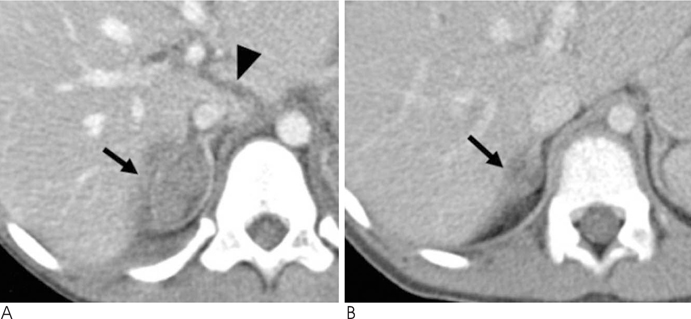

We identified 27 children (7.5%) (17 boys and 10 girls, mean age: 9.9 years, range: 2-18 years) with adrenal injury. The causes of adrenal injury were a traffic accident for 20 patients (74%), falls for four patients (15%) and blunt trauma for three patients (11%). The right adrenal gland was injured in 20 patients (74%), while the left adrenal gland was injured in three patients and bilateral involvement was noted in four patients. The patterns of adrenal injury were round or oval shaped hematoma in 23 lesions (74%), irregular hemorrhage with obliterating the gland in six lesions (19%) and active extravasation of contrast material from the adrenal region in two lesions (7%). Concomitant injuries were noted in 22 patients (81%), including 15 patients with liver laceration (56%), 11 patients with lung contusion (41%) and nine patients with renal injury (33%).

The frequency of adrenal injury was 7.5%. The right adrenal gland was more frequently involved. Concomitant organ injury was noted 81% of the patients and the most frequently involved organ was the liver (56%).